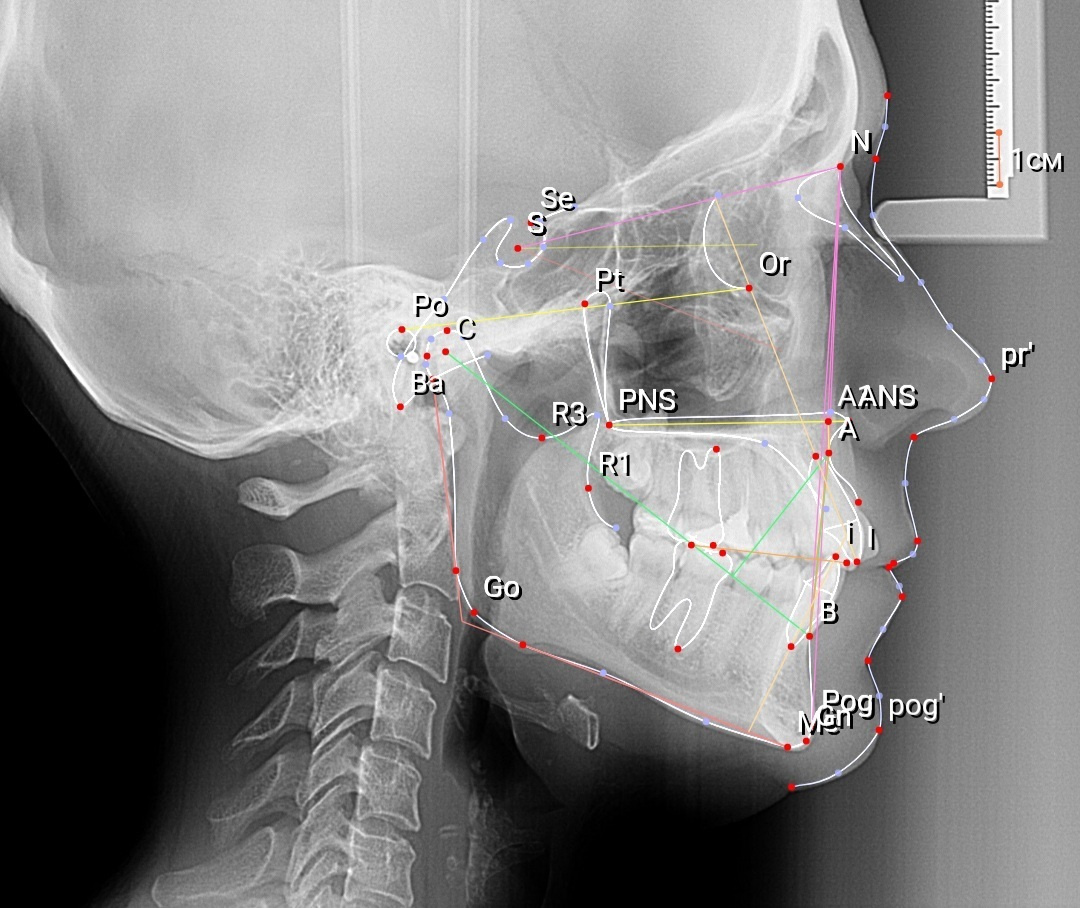

Пример расчета ТРГ

Заключение по исследованию ТРГ